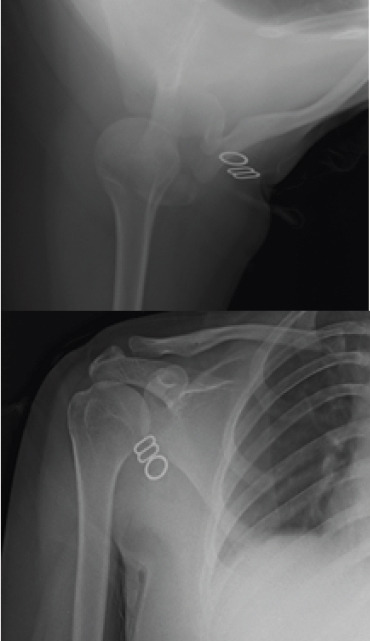

Treatment and outcome: Management included temporary immobilization and physiotherapy using the Watson multidirectional instability protocol focused on scapular motor control retraining. After 10 weeks, the patient showed marked improvement with restoration of overhead abduction and full external rotation. Radiographs confirmed proper joint alignment, and the patient resumed normal activities symptom-free.